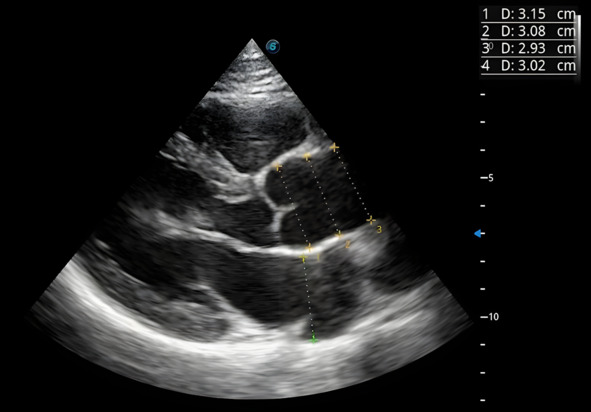

Аорту необходимо измерять в четырех точках: фиброзное кольцо, синусы Вальсальвы, синотубулярное соединение и проксимальная часть – восходящая часть аорты. Из них только фиброзное кольцо измеряется в систолу, остальные параметры в диастолу, когда створки аортального клапана закрыты. На этом этапе необходимо перемотать изображение на фазу диастолы.

С каждого изображения мы должны получить максимум информации. Проводим перпендикуляр, измеряем синусы Вальсальвы, затем синотубулярное соединение и восходящую часть аорты – ее максимальную часть. Все измерения видны на рисунке 3: синусы Вальсальвы – 3,1 см, восходящая часть аорты – 2,93 см, а синотубулярное соединение – 3,0 см. Здесь же можно измерить линейный размер левого предсердия, для этого мы проводим перпендикуляр и делаем замеры, в данном случае получили ровно 3 см (рис. 3).

Рис.3